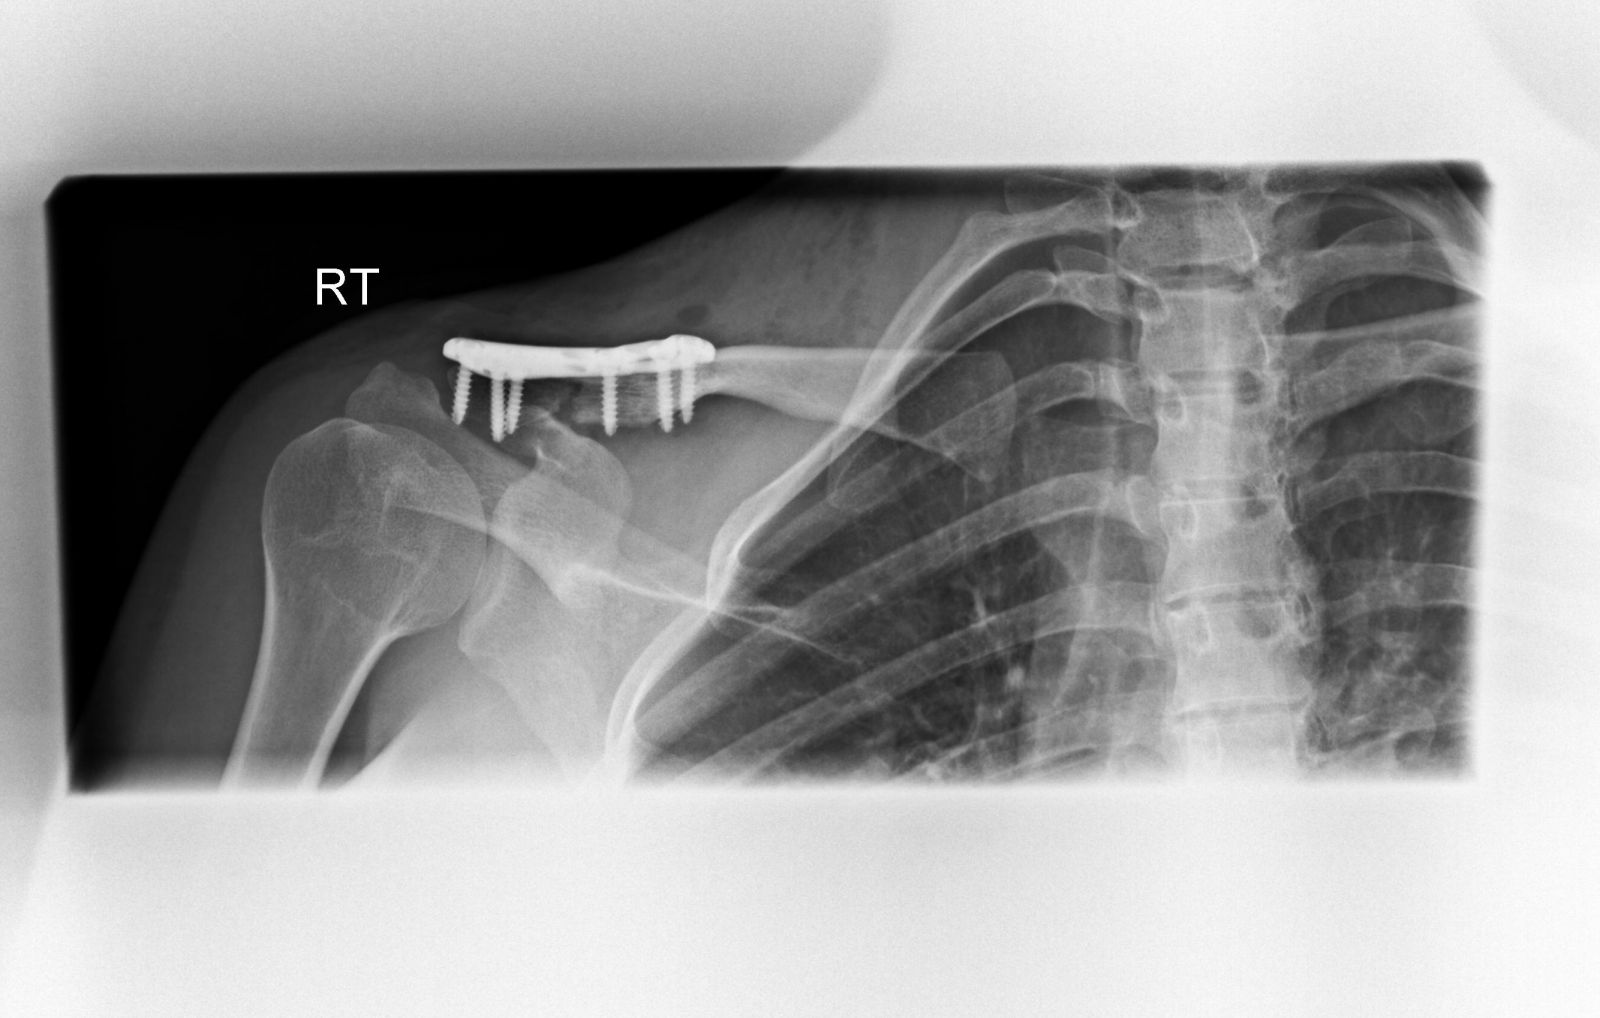

Η οστεοσύνθεση γίνεται κυρίως με χρήση πλάκας και βιδών (κοχλίες). Η πλάκα διαθέτει οπές (τρύπες), μέσα από τις οποίες εισάγουμε τις βίδες στα διάφορα τμήματα της κλείδας και τα συγκρατούμε στην ανατομική τους θέση. Η κατασκευή πλάκα-βίδες-κλείδα είναι πολύ σταθερή και επιτρέπει την πώρωση του κατάγματος σε λίγες εβδομάδες.

Μετεγχειρητικά, οστεοσύνθεση κατάγματος και αποκατάσταση κορακοκλειδικών συνδέσμων